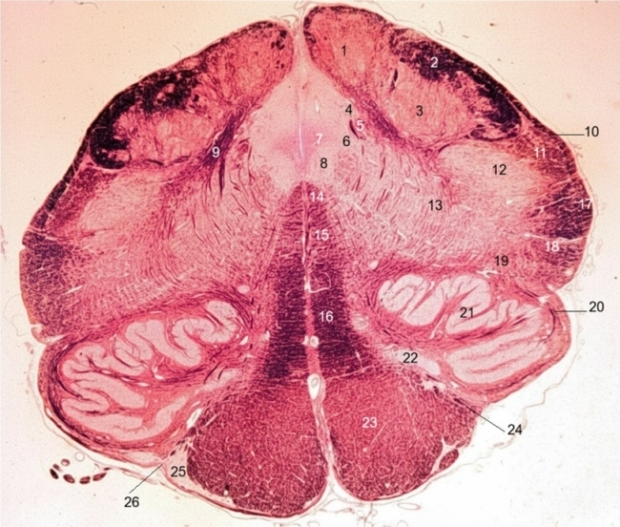

1. Gracile nucleus

2. Cuneate fasciculus

3. Cuneate nucleus

4. Solitary nucleus

5. Solitary tract

6. Dorsal motor nucleus of vagus

7. Dorsal longitudinal fasciculus

8. Hypoglossal nucleus

9. Internal arcuate fibers

10. Dorsal spinocerebellar tract

11. Spinal trigeminal tract

12. Spinal trigeminal nucleus

13. Nucleus ambiguous

14. Medial longitudinal meniscus

15. Tectospinal tract

16. Medial lemniscus

17. Ventral spinocerebellar tract

18. Spinal lemniscus

19. Lateral reticular nucleus

20. Central tegmental tract

21. Inferior olivary nucleus

22. Medial accessory olivary nucleus

23. Pyramidal tract (corticospinal tract)

24. Intra-axial root fibers of hypoglossal nerve

25. Arcuate nucleus of medulla

26. Preolivary sulcus